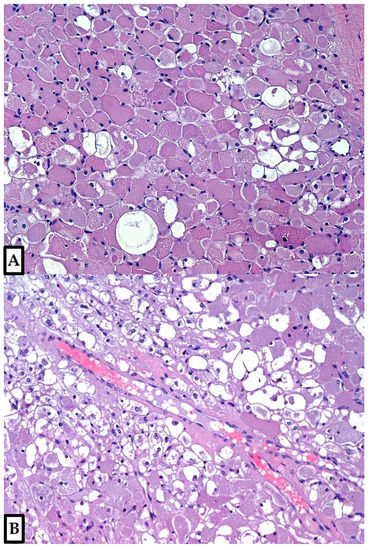

Figure 3. The tumor was composed of large polygonal cells of variable size and shape, with abundant granular eosinophilic cytoplasm; vacuolated cells (spider cells) were usually dispersed through the tumor (A), occasionally concentrated in some areas (B). Vascularization included small, sometimes dilated capillaries and occasional ectatic medium-sized vessels (Hematoxylin and Eosin, 10×; previously unpublished, original photos).